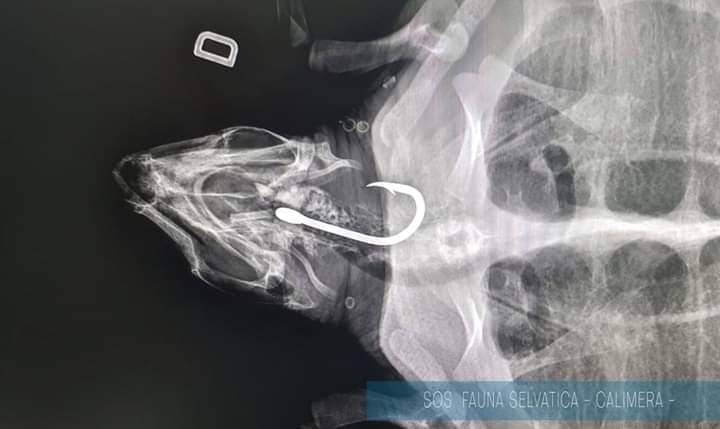

Delicato intervento per salvare la vita ad una Caretta Caretta ospite del Centro Recupero Fauna di Calimera. L’equipe di veterinari del Centro Veterinario Lupiae (Gianluca Nocco, Egidio Però ed Etta Mans), ha lavorato fino a tarda notte per estrarre l’amo da pesca che la tartaruga aveva ingerito e che si era infilzato nella trachea.

Lion il nome dell’esemplare è affidato ora alle cure del Centro Recupero in attesa di tornare in libertà. Lion è stata ritrovata spiaggiata a San Foca, marina di Melendugno l’8 gennaio scorso, recuperata da Anna Leone e Alfonso Ingrosso insieme a Mario Congedo del Corpo Forestale ed affidata al Centro che ricovera tutti i selvatici, non solo tartarughe.